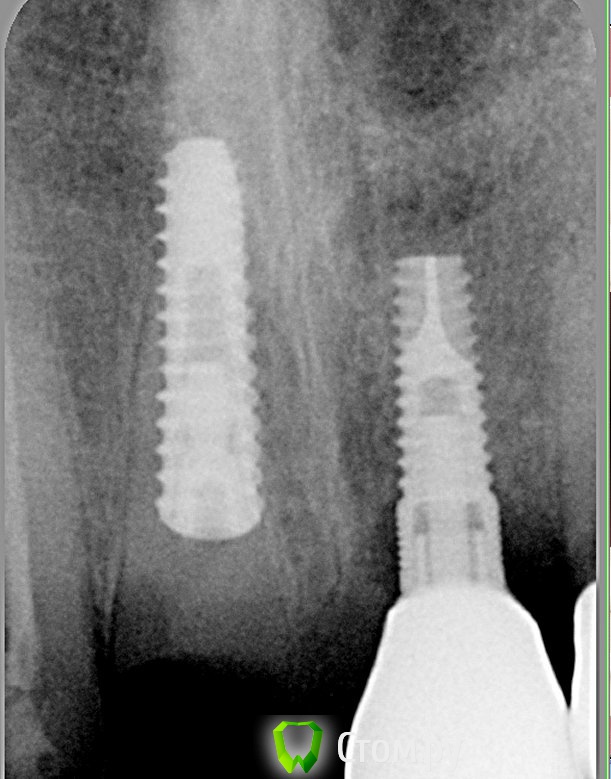

Andex Опубликовано 7 октября, 2014 Поделиться Опубликовано 7 октября, 2014 Внесу свой взгляд на тему. Мне интерестна методика - выкладываю свой кейс. Солидарен с Александром, если Вам интерестно - могу поделиться результатами и наблюдениями своих пациентов. На последнем фото - установил формирователь, тк через неделю после операции разошлись швы и сместился мною плохо мобилизованный ротированный(недостаточно) лоскут с неба - мои навыки еще далеки от идеала. Ссылка на комментарий

Andex Опубликовано 8 октября, 2014 Поделиться Опубликовано 8 октября, 2014 (изменено) а почему в этом случае отдали предпочтение щитку?Конфигурация гребня хорошая, рядом коронка на болте в хорошем состоянии, вкрутил бы болт немедленно + графт в щель + сст, + врем коронка. ИмХоМне понравилась теория данной методики- поэтому я пока отношусь к числу людей,кто верит в щит. Рядом винт - тоже моя работа, сделал специально 2 зуба рядом в одинаковых условиях(на одном пациенте), чтобы динамику в сравнении наглядно вести. Графт+сст+времянка - пока считаю свой уровень недостаточным для таких продвинутых методик, в основном из-за сст,тк не научился еще с ним работать как надо(( Изменено 8 октября, 2014 пользователем Andex 1 Ссылка на комментарий